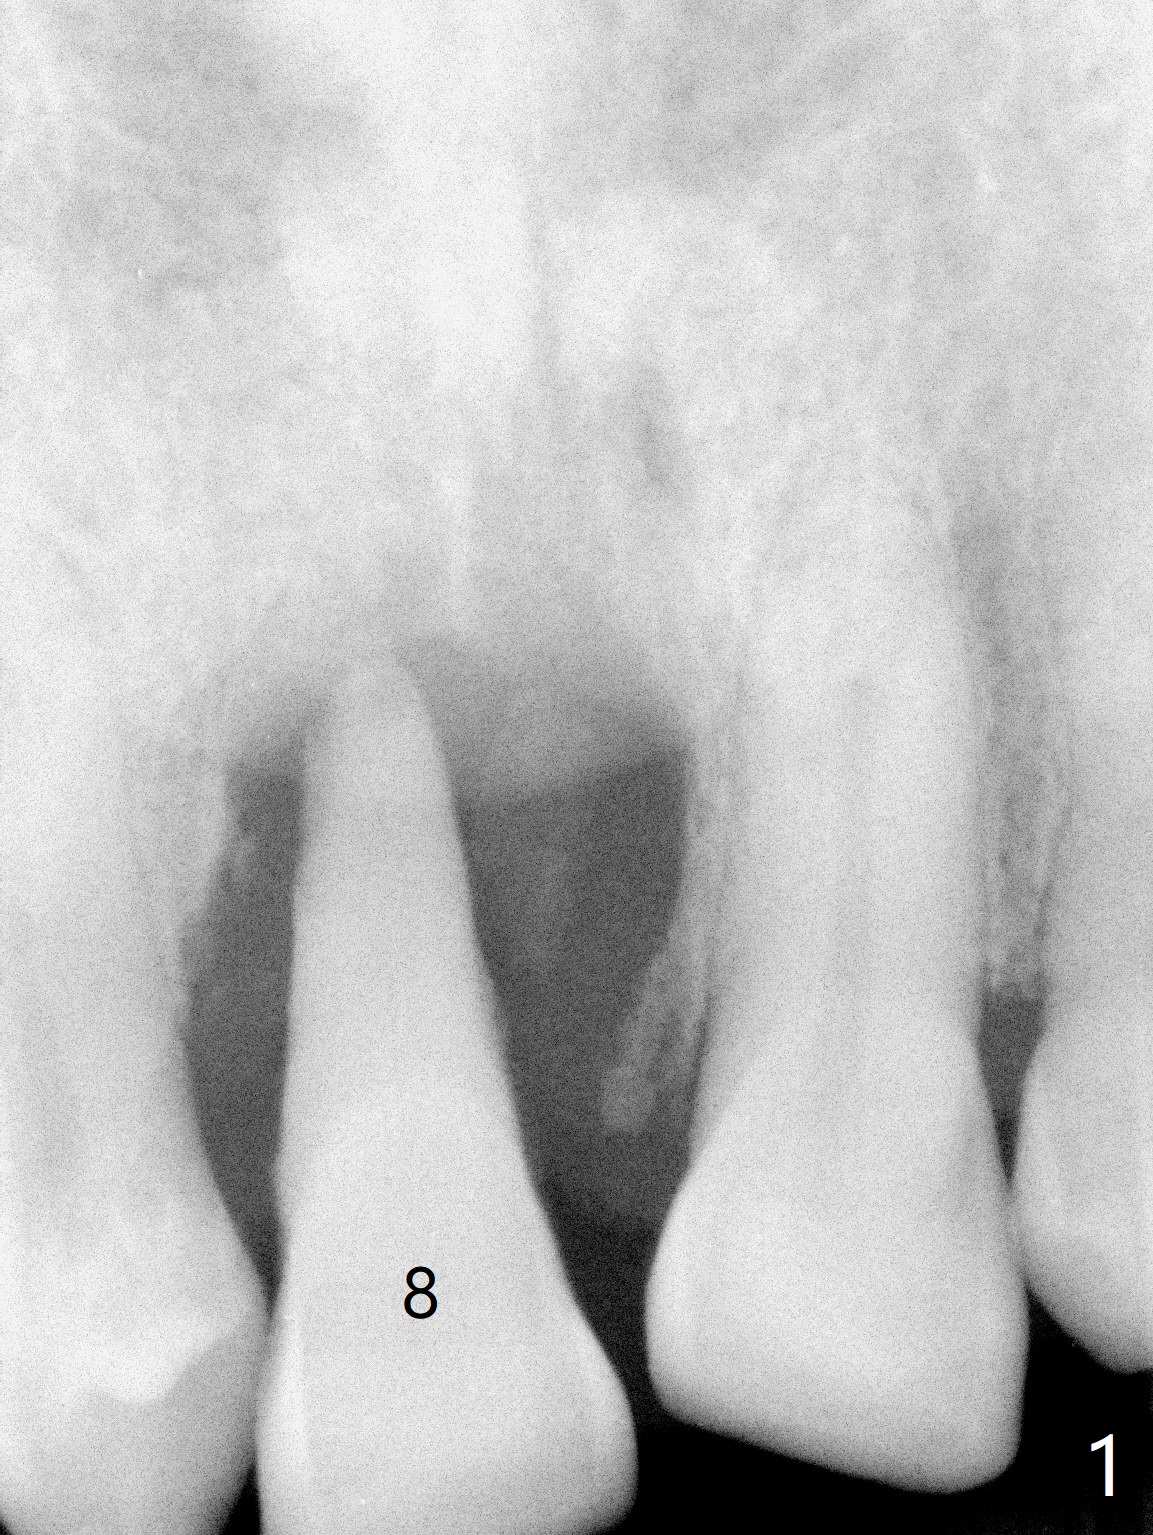

A 69-year-old man (ex-soldier) had the tooth #8 extracted for a flipper nearly 8 years earlier (Fig.1 (obliterated canal)). A denture tooth is added at #14 after extraction in NY a few years later (Fig.2). In spite of sufficient bone width at #8, a 2.5x10 mm mini implant will be chosen to reduce the chance of palatal thread exposure (Fig.3 P). A 5x8.5 mm implant will be placed at #14 to achieve enough stability and not cause sinus complication (Fig.4). Take preop photos to show the anterior deep overbite and overjet. In fact the patient canceled the surgery. Two years later, he returns with history of right TMJ dislocation, which may be related to reduced mastication efficiency and partial edentulism (Fig.5,6).